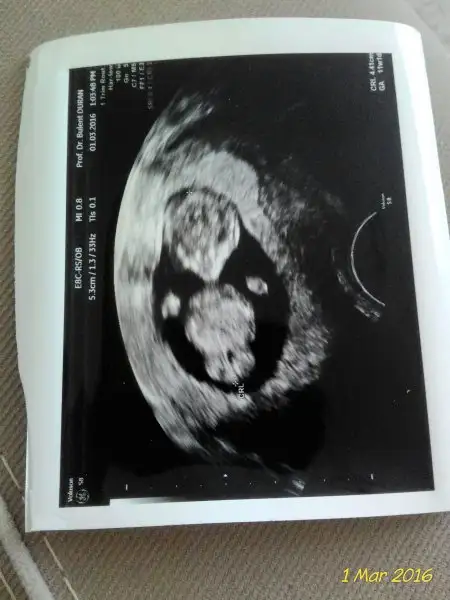

Alttan bakildiysa erkek olma ihtimalini gosteriyorGünaydın kızlar..geceden beri okuyorum yazıları en başından. Uyuya kalmışım .şimdi tekrar bakayım dedim heyecan yaptırdınız bana da . Şu an 6+5im ama size 5+5lik foto atıcam bi bakın bakalım. Alttan bakıldı bu arada

Peki bunun icin ne diosunuz. Karindan ultrason 6+5resmi saat yönüne çevirip bakacaksın cnm herzaman saat yönüne patlıcan oldu mu ... yani demin sivri dedim doğru anlatamadım saat yönüne çevireceksin.

Teoriye göre kız bebek olması gerekiyor. HayirlisiPeki bunun icin ne diosunuz. Karindan ultrason 6+5

Teoriye göre kız bebek olması gerekiyor. Hayirlisi